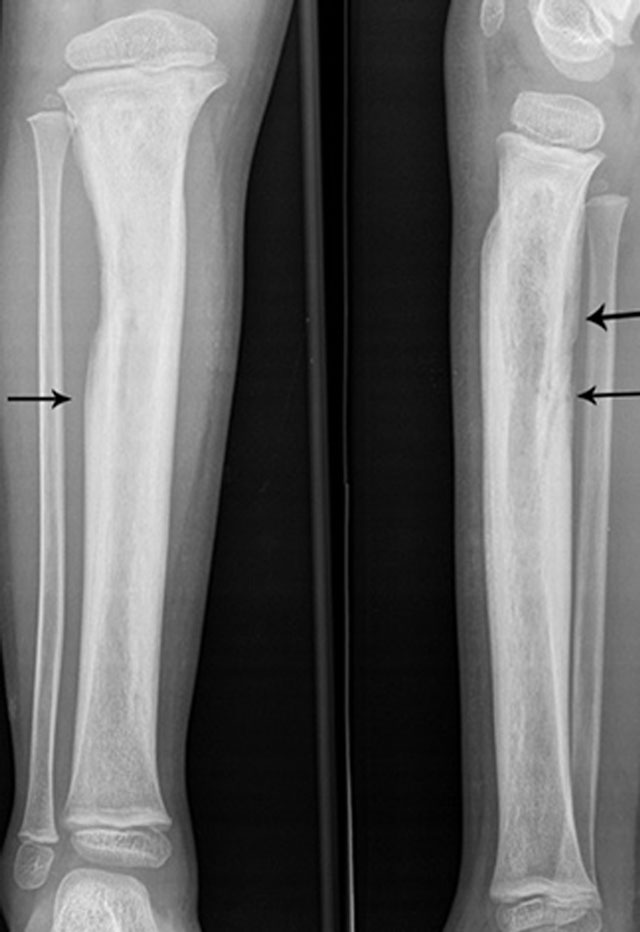

Extensive involucrum on plain radiography. Anteroposterior and lateral plain radiography showing extensive involucrum (arrow) at the tibial diaphysis (black arrows).

Inhomogeneous osteosclerosis and/or sequestrum formation (necrotic bone) is characteristic for chronic osteomyelitis on plain radiography. A sequestrum represents a segment of necrotic bone that is separated from the living bone by granulation tissue and bone resorption. It is typically denser than the living bone [13]. In some cases, a layer of new periosteal bone or involucrum is formed around the necrotic bone (Figures 7, 11, 12). On MRI, a sequestrum is hypo-intense on all pulse sequences. Gadolinium contrast administration may reveal a cloaca (opening in the involucrum) through which pus, granulation tissue and sequestra can be discharged. In addition, enhancement of sinus tracts tracking from the bone to the skin surface is well demonstrated on contrast enhanced MRI (Figure 13) [15].